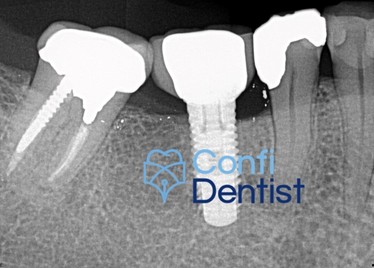

4 / 27

4. (Select ONE OR MORE correct answers)

What observation(s) can be made for tooth 3.6?